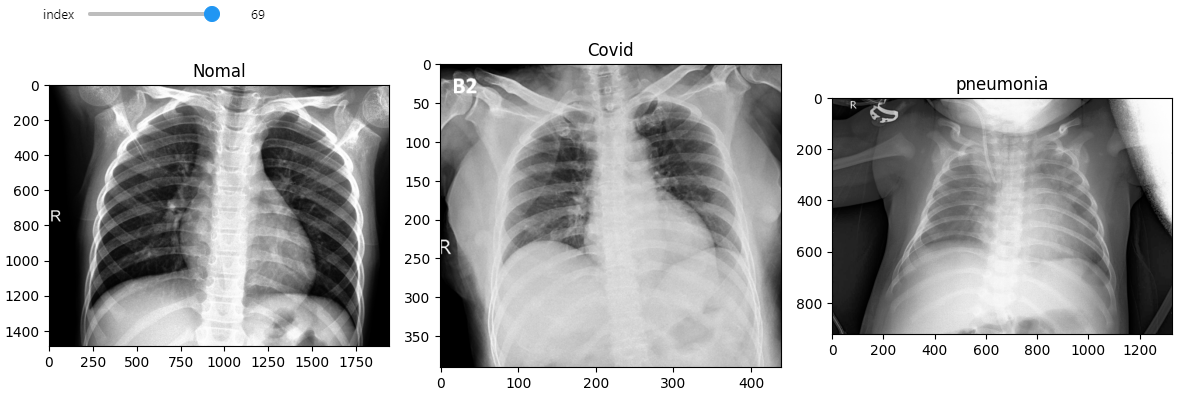

@interact(index=(0, min_num_files-1))

def show_samples(index=0):

normal_image = get_RGB_image(data_dir, normals_list[index])

covid_image = get_RGB_image(data_dir, covids_list[index])

pneumonia_image = get_RGB_image(data_dir, pneumonia_list[index])

plt.figure(figsize=(12, 8))

plt.subplot(131)

plt.title("Nomal")

plt.imshow(normal_image)

plt.subplot(132)

plt.title("Covid")

plt.imshow(covid_image)

plt.subplot(133)

plt.title("pneumonia")

plt.imshow(pneumonia_image)

plt.tight_layout()